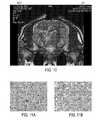

FIGS. 11A and 11B represent a histologic cross section of swine brain after infusion of 450 microliters of normal saline which demonstrated Pyknotic neurons and ballooning neurons indicating unacceptable damage to neural tissue.FIG. 11B provides a partial view ofFIG. 11A and which is set at a higher magnification.

FIG. 11 represents a histologic cross section of swine brain after infusion of 450 microliters of normal saline which demonstrated pyknotic neurons and axonal swelling indicative of neuronal injury. While none of the animals exhibited clinical evidence of neurologic dysfunction, histologic analysis of brains within 1 week and after 1 month of infusion demonstrated mild, microscopic injury to neurons, which likely resulted from the osmotic gradient between the normal saline infusate which is hypertonic to the swine brain and CSF.FIG. 11B provides a partial view ofFIG. 11A and which is set at a higher magnification.

Accordingly, this preliminary study confirms the concept that convection-enhanced delivery (CED) of saline leads to a differential uptake of water content in grey and white matter with enhanced MRI visualization of deep brain anatomy similar to what was observed in the patient with edema from a localized infectious process. Backflow along the catheter track in one animal led to a failed attempt highlighting the need to improve certain approaches of a microcatheter. Histological analysis revealed unexpected neuronal injury from normal saline which is hypertonic and illustrates the need to test and optimize additional infusates.